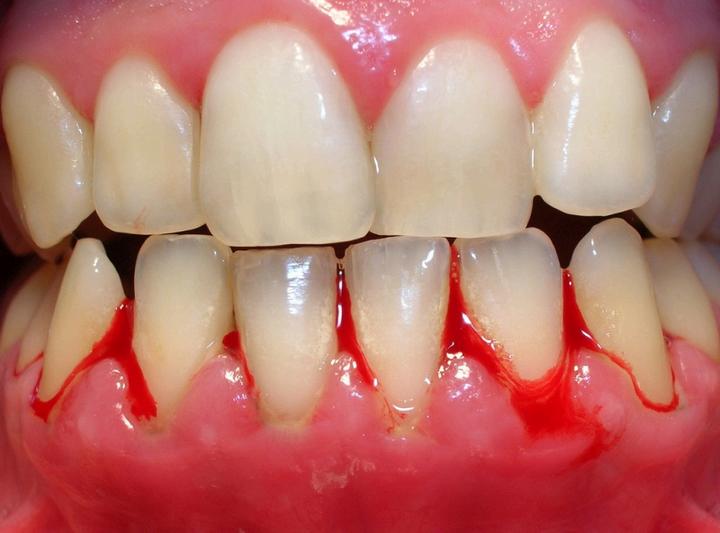

Sintomas

Encias rojas o inflamadas

Dolor, sangrado en las encias

Bacteriasprovocanunenrojecimientoy sangradodelasencíasypuedenllegara causarlesionesgravesalostejidos.